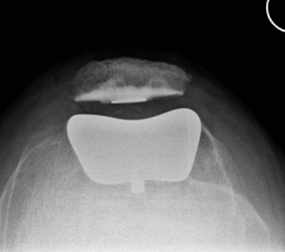

Das Kniegelenk besteht aus drei Gelenkkompartimenten: einem inneren, zentralen und äußeren Kompartiment. Die Kniescheibe bildet ein Widerlager und gleitet über den Oberschenkelknochen. Prinzipiell ist ein isolierter oder kombinierter Verschleiß vom inneren oder äußeren Gelenkkompartiment sowie auch dem Kniescheibenwiderlager möglich. Erkennt man die Erkrankung früh genug und ist der Leidensdruck entsprechend, so kann man die einzelnen Kompartimente isoliert ersetzen.

Wir halten ein großes Portfolio moderner und bewährter Prothesen vor, die sich entsprechend den o.g. Ausführungen vom Prothesendesign unterscheiden. Innerhalb des Designs liegen verschiedene Ausführungen und verschiedene Größen vor, so dass wir je nach Krankheitsbild für Sie eine individualisierte Versorgung anbieten können. Bei entsprechender Indikation kann der Kniegelenkersatz auch mit robotischer Unterstützung erfolgen, die Prinzipien werden in dem nachfolgenden Artikel aus FOCUS-Gesundheit 5/2023 verständlich dargestellt.

Sollte bei Ihnen eine Endoprothese in Frage kommen, wird durch Beurteilung verschiedener Faktoren der Prothesentyp aus dem o.g. Portfolio für Sie ausgesucht.